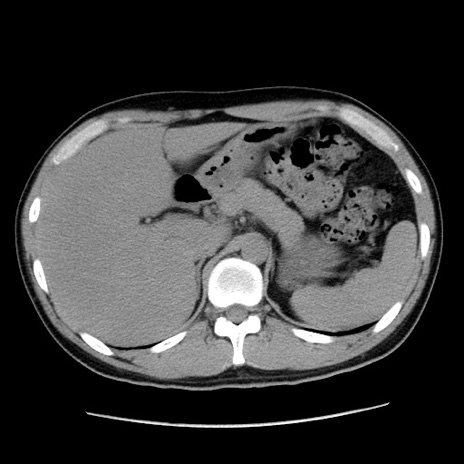

冠状断像

【症例】20歳代 男性

【主訴】心窩部痛

【現病歴】今朝より上腹部痛あり。一旦軽快していたが再度出現したため救急要請。昨日夕に白身の魚を含む刺身を食べた。

【身体所見】BP 136/89mmHg、HR 74/min、BT 37.0℃、腹部:膨満、軟、心窩部に圧痛あり。反跳痛なし、筋性防御なし、腸雑音やや亢進あり。

【データ】WBC 17700、CRP 0.48